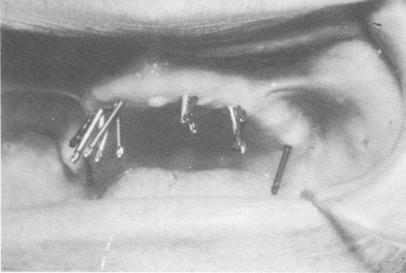

that they could be driven deeper into the bone and made more divergent from each other. Broader angulation of the protruding pin heads and fastening of the pin heads with acrylic resin, eliminating the Teflon, was accomplished. Here the ends of the pins, instead of being bent parallel to each other, were left extended in their diverging positions (Fig. 10-218).

Fig. 10-218. Pins were driven in various directions through the soft tissue and into the bone.